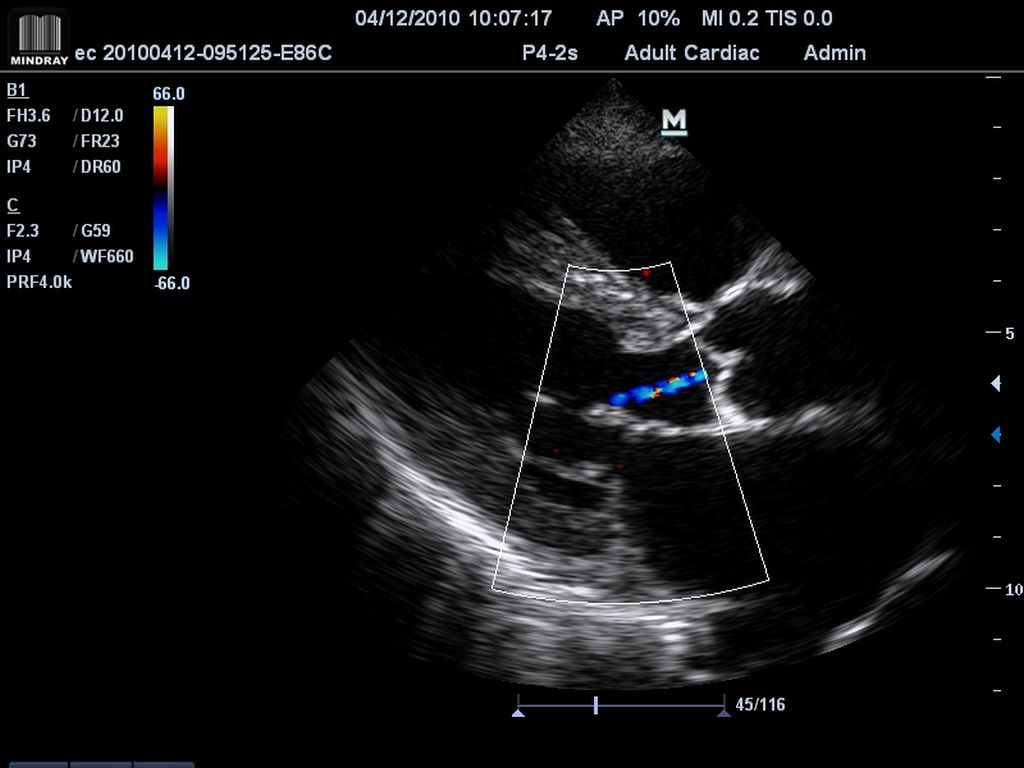

Klinické obrázky:

- High Sensitivity Flow

- 2 živé obrazy B/CFM (Dual live B/CFM mód)

- Pulzný, Spektrálny Doppler (PW), citlivý Farebný Doppler (CFM), ultracitlivý smerový Power Doppler (PDI), anatomický - M mód a Stress Echo